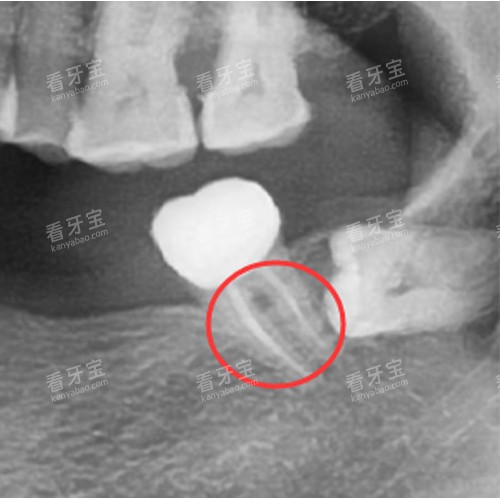

报销“预审核”服务:患者可通过欢笑口腔公众号上传X光片,系统自动计算报销金额,避免“先自费后报销”的资金压力。